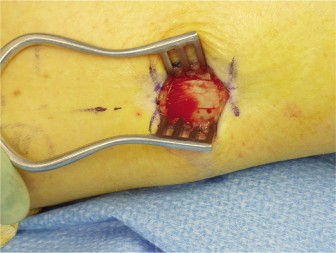

A 52-year-old female with a past medical history significant for long-term type 2 diabetes presents with a ri…